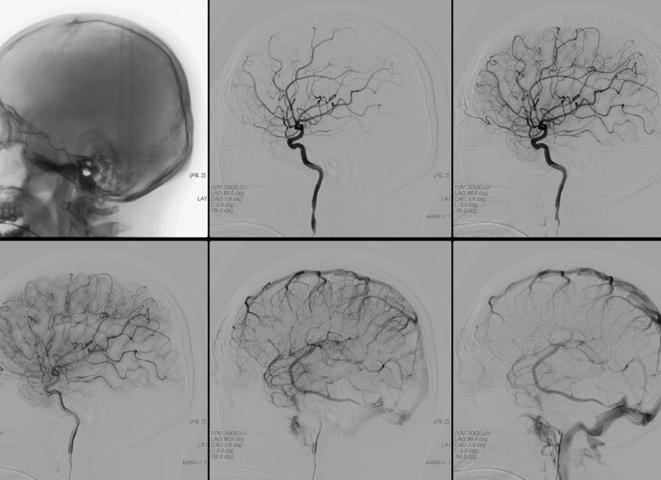

- Ангиография. Методика предназначена для изучения патологических процессов в сосудах. В кровь обследуемого вводят специальный контраст, после чего выполняется рентгеновский снимок.

Для того чтобы окончательно подтвердить диагноз, может понадобиться мрт, а также ангиография сосудистой системы. С помощью этого метода оценивается состояние уплотнений на стенках.